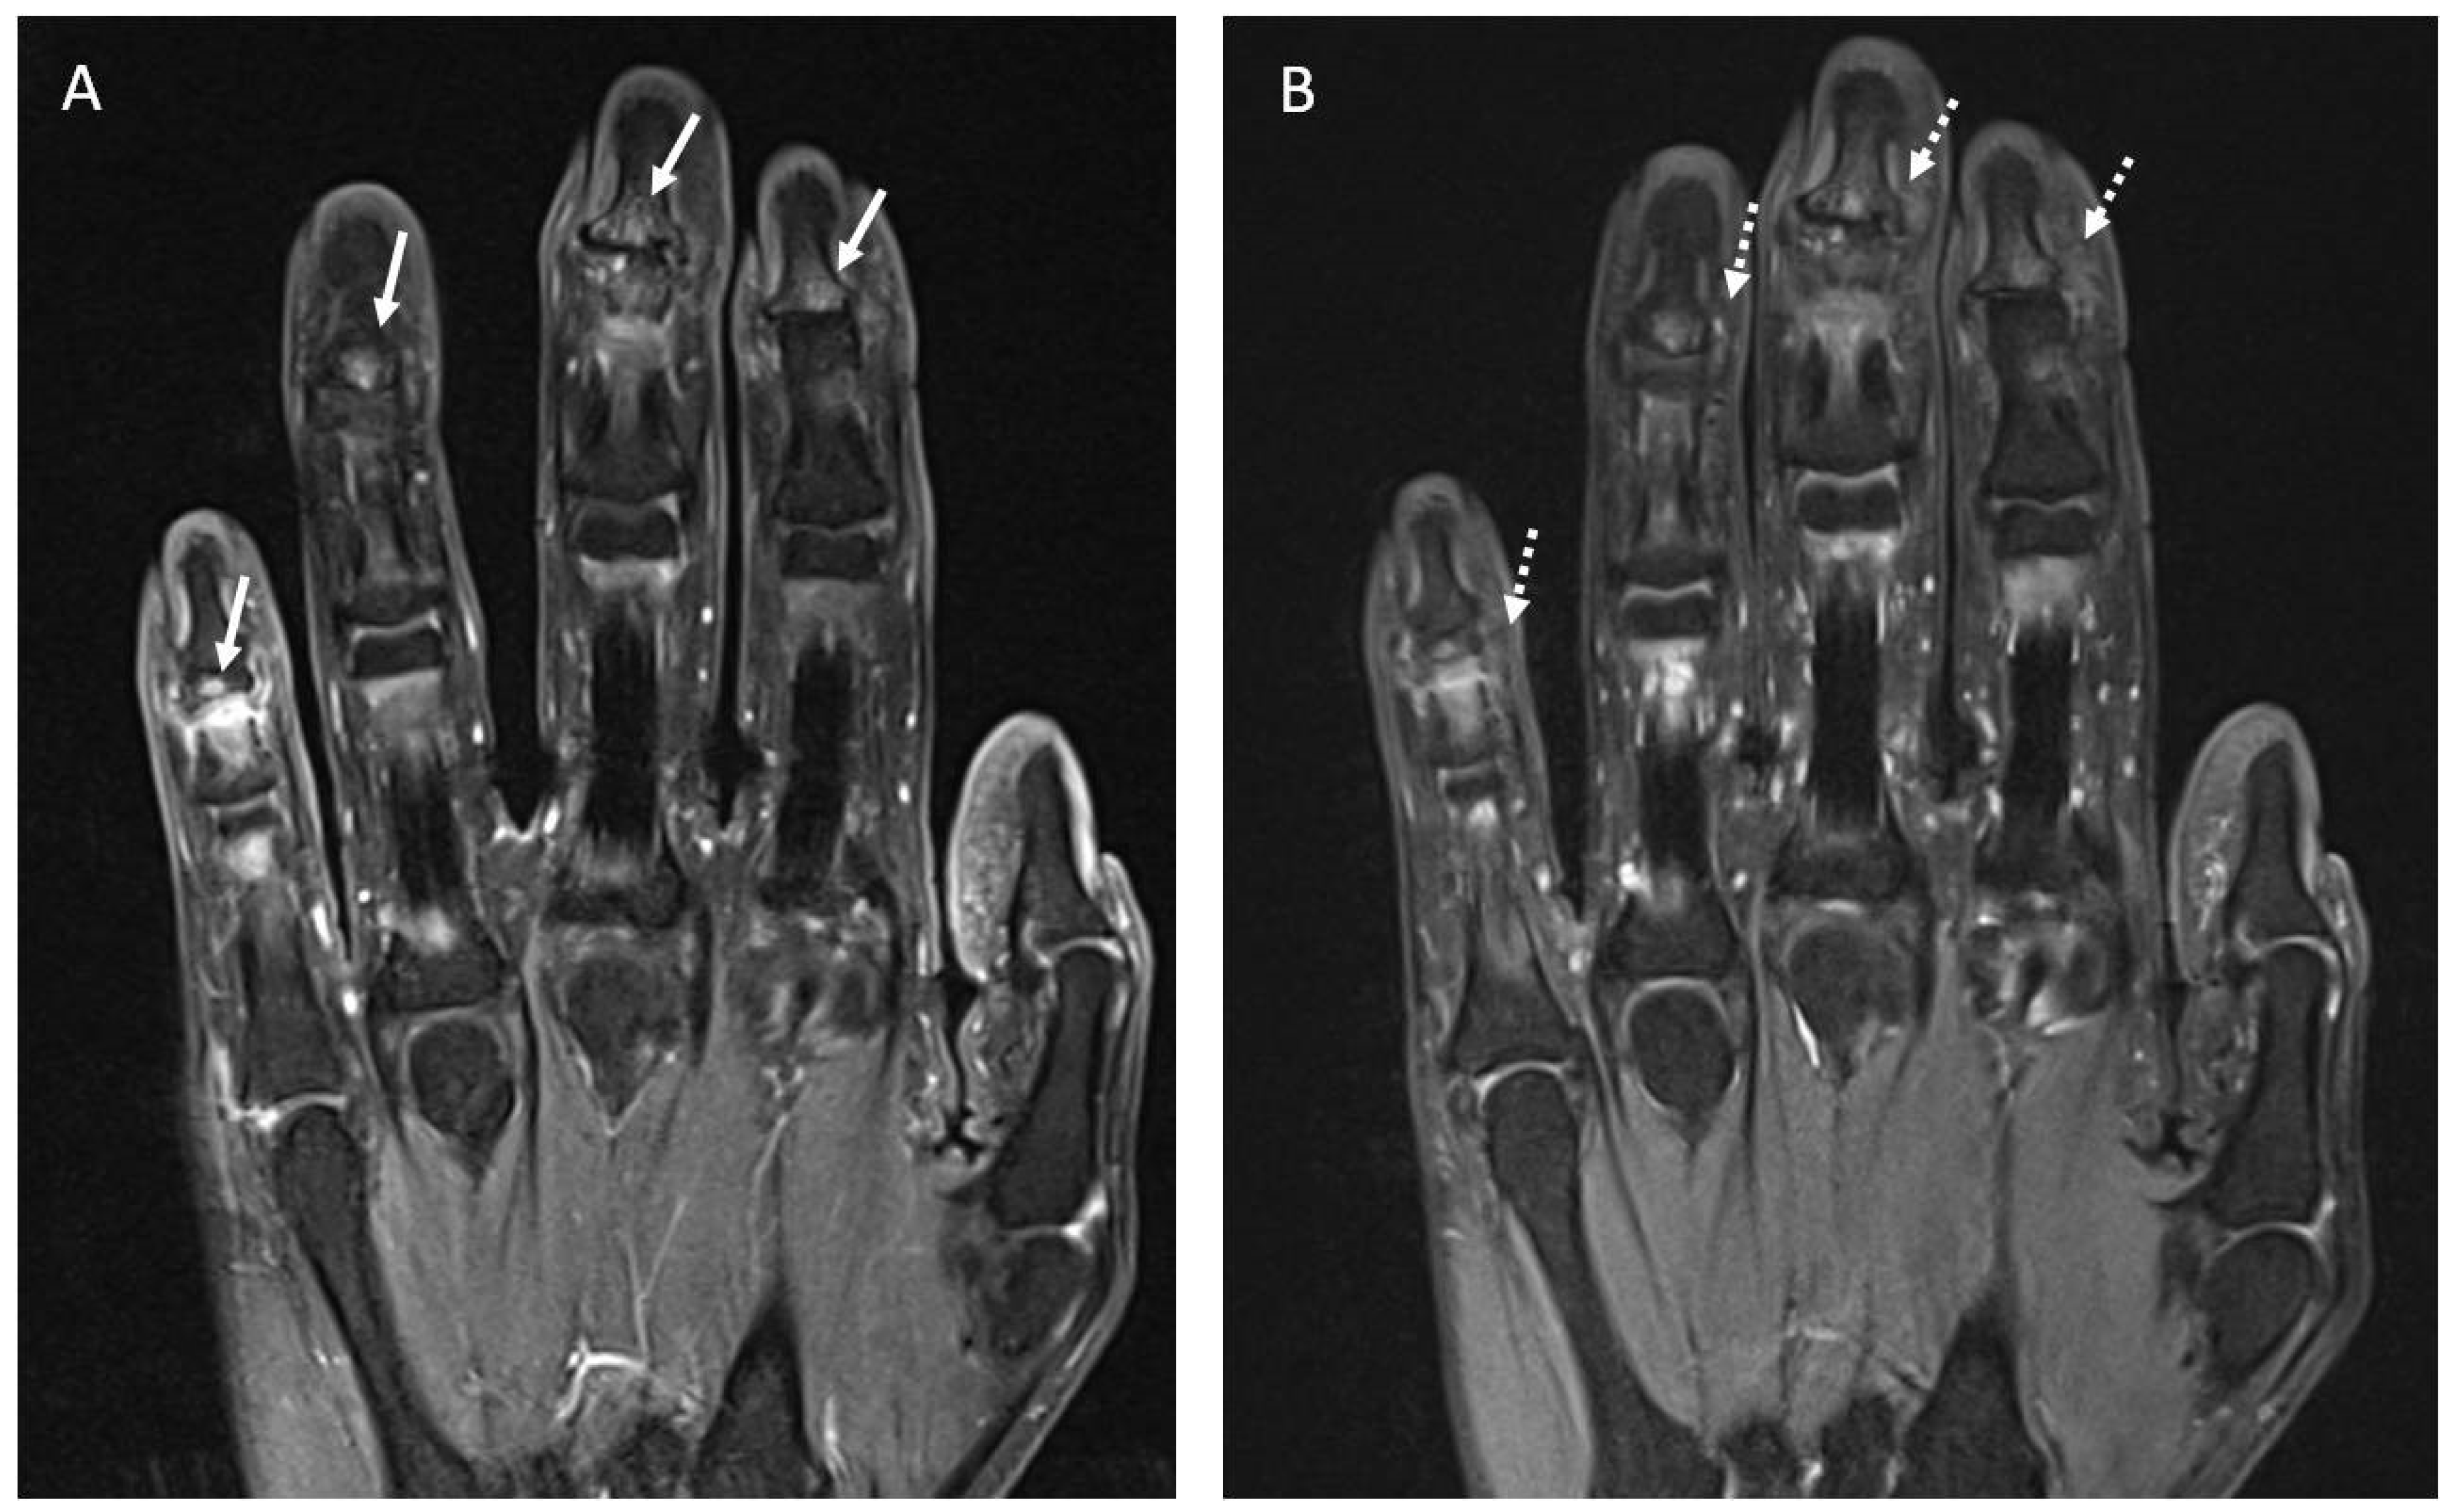

Four patients underwent MRI assessment. Two patients received treatment with Anti-TIM3, one with Pembrolizumab, and one with Durvalumab. In these patients, ICI-induced arthritis appeared after a mean time of 15.5 months. Abnormal findings were reported in three out of four patients, all in accordance with clinical symptoms. One patient presented with a PsA-like pattern and had signs of distal bone edema in the fingers (Figure 5). No erosions or myofascitis were reported. The general characteristics of previous cases reported with rheumatic irAEs and MRI assessment are shown in Supplementary Table S1.

Figure 5.

(A). Coronal fat suppressed T1-weighted image of the hand following IV contrast administration shows small areas of contrast enhancement of the subcortical articular margin (arrows) of the distal interphalangeal joints in the second, third, fourth and fifth fingers consistent with inflammatory activity. (B). Coronal fat suppressed DP-weighted image of the hand shows areas of bone edema of the subcortical articular margin (dashed arrows) of the distal interphalangeal joints in the second, third, fourth and fifth fingers.